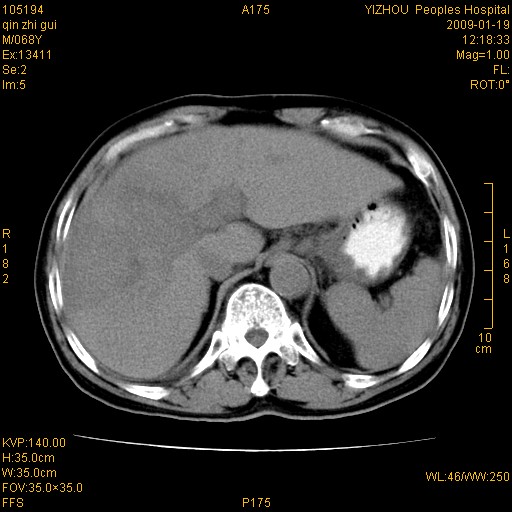

以下是引用随光逐影在2009-1-21 16:11:00的发言:[br]1)考虑肝右叶肝癌并肝静脉及门静脉瘤栓形成。2)肝硬化,少量腹水。3)胆囊炎。4)右侧少量胸腔积液。

病灶外缘凹凸不平,平扫低密度,增强动脉期有强化,门脉早显,静脉期及延期呈延迟强化,结合病史考虑右肝前叶巨块型肝癌可能性大,强化表现不除外胆管细胞癌